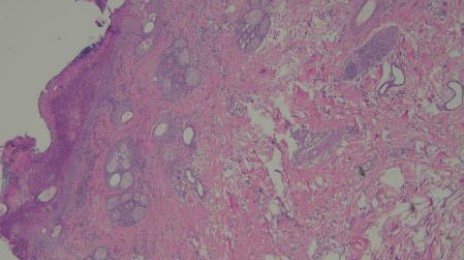

組織病理結果為化膿性嗜酸球性真皮炎,如圖四所示。排除感染的問題,提高prednisolone劑量到3mg/kg sid,兩週後硬皮病灶消失、搔癢症狀緩解,開始逐漸減量類固醇,目前1mg/kg qod狀況良好如圖五所示,持續治療。

A B

C D

圖四:A, 檢體為表皮層到真皮層組織,少部分表層皮下脂肪有涵蓋在檢體內。B, 表皮結構完整,表面有大量的壞死細胞碎片、片狀角質、脫落的角化細胞覆蓋或是形成沒有破裂的膿皰結構,皮膚糜爛但局限於表皮,基底膜完整。C, 真皮層輕微水腫,有少量到中等量、零散分布的發炎細胞浸潤,細胞有略微分布表層真皮或是毛囊腺體周圍的傾向,但不明顯。D, 浸潤的細胞以嗜中性球、嗜酸性球以及肥大細胞為主,血管內也可見到數量明顯增加的嗜中性球及嗜酸性球,皆為分化成熟沒有惡性特徵。D, 表皮層中有見到一顆凋亡細胞 (apoptotic cell),但周邊沒有淋巴細胞包圍。E, 此外毛囊腺體的結構完整,沒有破裂,毛囊內也沒有見到細菌、黴菌或是寄生蟲。以特殊染色B&B檢查檢體,沒有見到細菌病原。